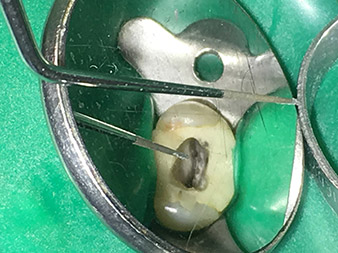

Traitement du canal radiculaire efficace et atraumatique

La conservation durable de la dentition est le principal objectif de l'endodontie moderne.

En plus du recours à des méthodes diagnostiques et thérapeutiques efficaces, l'utilisation des derniers outils et instruments techniques joue un rôle clé dans la réussite des soins aux patients. Le Dr Shahrad Nouraie Ashtiani et son équipe, qui exercent en cabinet à Brême, en Allemagne, traitent jusqu'à dix cas d'endodontie par semaine. L'aspiration des patients à un traitement le plus atraumatique possible associé à un bon pronostic de réussite constitue un défi quotidien pour le dentiste et interne en chirurgie orale qui a choisi l'endodontie comme spécialité.

Pour le Dr Nouraie Ashtiani, fervent utilisateur de la gamme élargie d'instruments W&H à ultrasons en endodontie, le traitement du canal radiculaire est non seulement plus efficace pour l'opérateur mais aussi moins astreignant pour le patient. L'expert en chirurgie dentaire maîtrise aisément même les situations les plus difficiles. Dans une interview récente, le spécialiste en endodontie nous a parlé des fonctions particulières qui caractérisent les instruments de W&H et a mentionné les risques possibles liés au traitement du canal radiculaire.